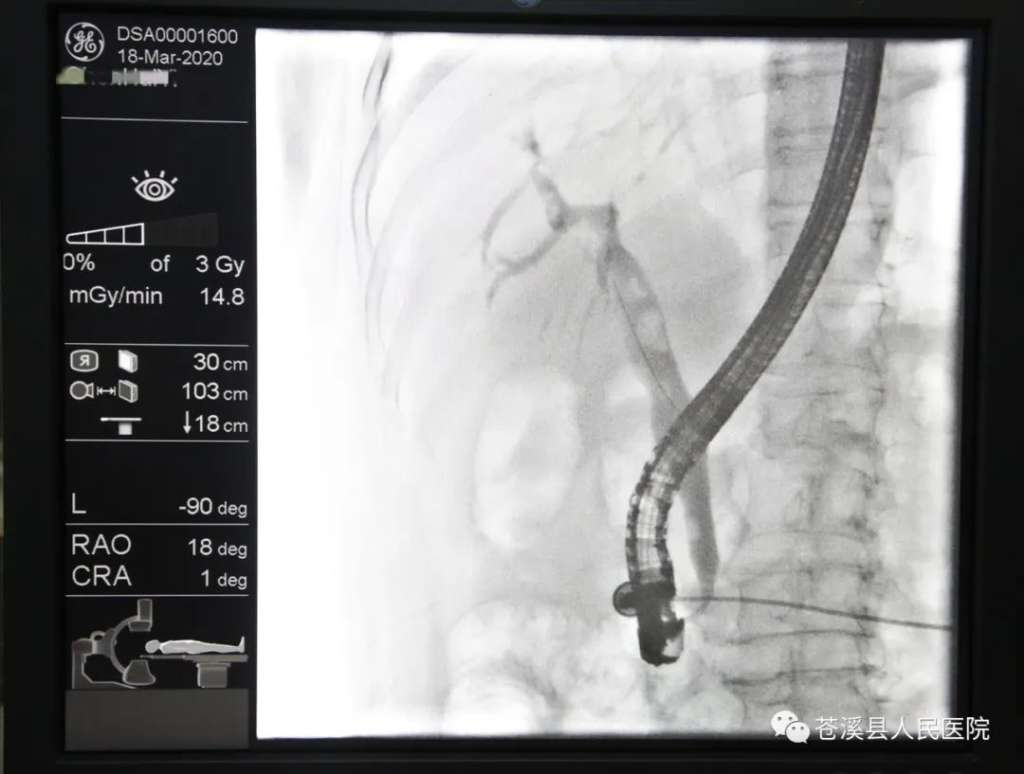

ercp术中胆道造影/放置鼻胆管引流

内镜逆行胰胆管造影(ercp)

ercp技术是治疗胆总管结石及梗阻性黄疸的先进微创方法